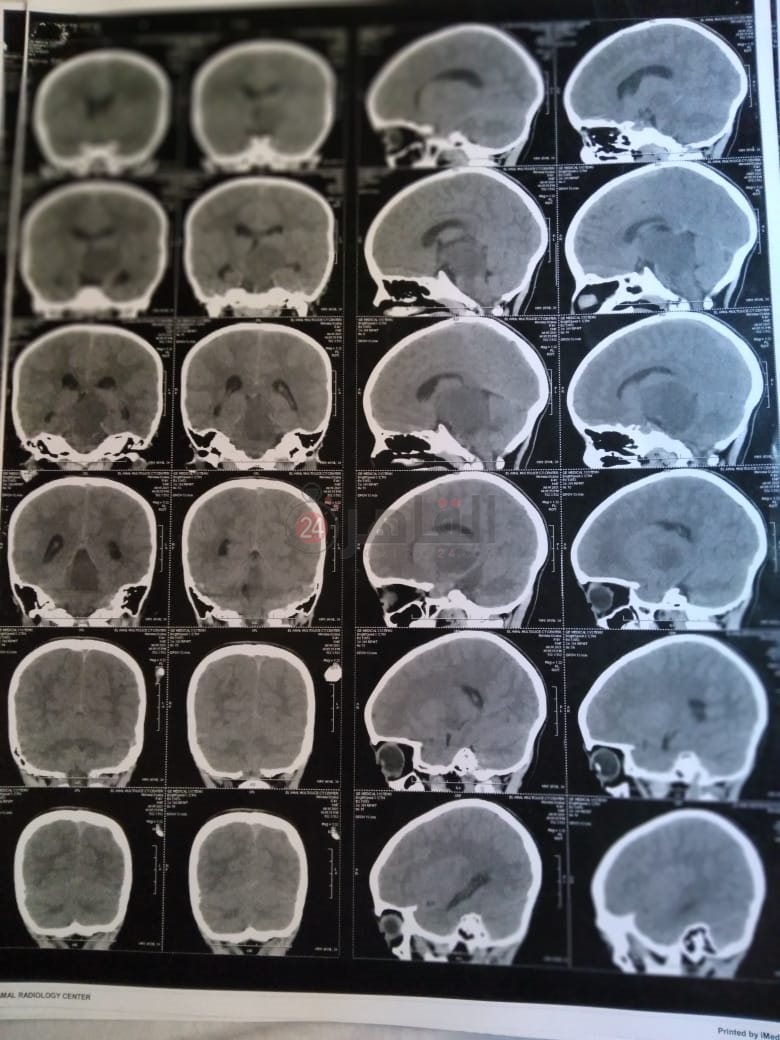

وأضاف: "أجرينا أشعة مقطعية لها لم يظهر بها أي شيء، ثم طلب الطبيب إجراء أشعة رنين على المخ، وهنا تبين وجود بؤرة سرطانية بالمخ، مشيرًا إلى أن:" الدكتور طلب مني أذهب إليه لوحدي من غير الأم والبنت، وقالي إن في ورم بس مش عارفين نوعه خبيث ولا حميد".

وأوضح أن حالة نجلته تتدهور بسرعة كبيرة، حيث أصُيبت حاليًا بشلل نصفي بالجانب الأيمن، لأن البؤرة حجمها 2.5 سم في 4.5 سم، ومرتكزة على جانبها الأيمن، مشددًا على أنها الحالة الأولى في العائلة التي تصاب بهذا المرض.